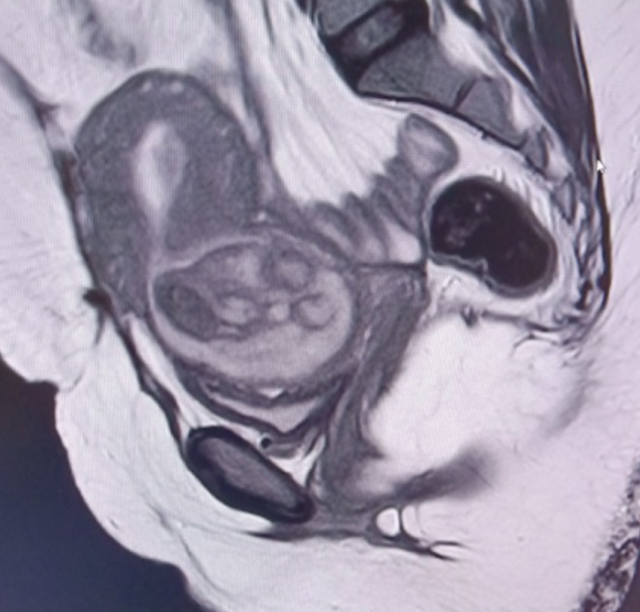

T2 images ( sag , cor &

axial) – show mixed signal fairly well defined oval shaped lesion in the low

anterior uterine segment extending into the cervix causing dilatation of the

cervix along with inferior bulge of the lower cervical lips causing effacement

of the posterior fornix of vagina with possible endocervical canal extension. Superiorly

thin extension of the T2 hypointense signal from the lesion into the

endometrial cavity was also seen. Lesion appears iso to hyperintense in T1 with

marked blooming areas within the lesion in GRE extending into the endometrial

cavity suggesting hemorrhagic contents in the lesion.

Focal grossly thinned out

anterior myometrium seen in the low uterine seg

-

ment ( LUS) showing broad

contact with the above mentioned lesion in LUS & cervix. No defect or any rupture was seen in the

uterine scar. No collection or any free fluid was seen in the parametrium.

Thick adhesion bands with T2 hypointense signal were seen between the anterior wall of

uterus & adjacent abdominal wall .